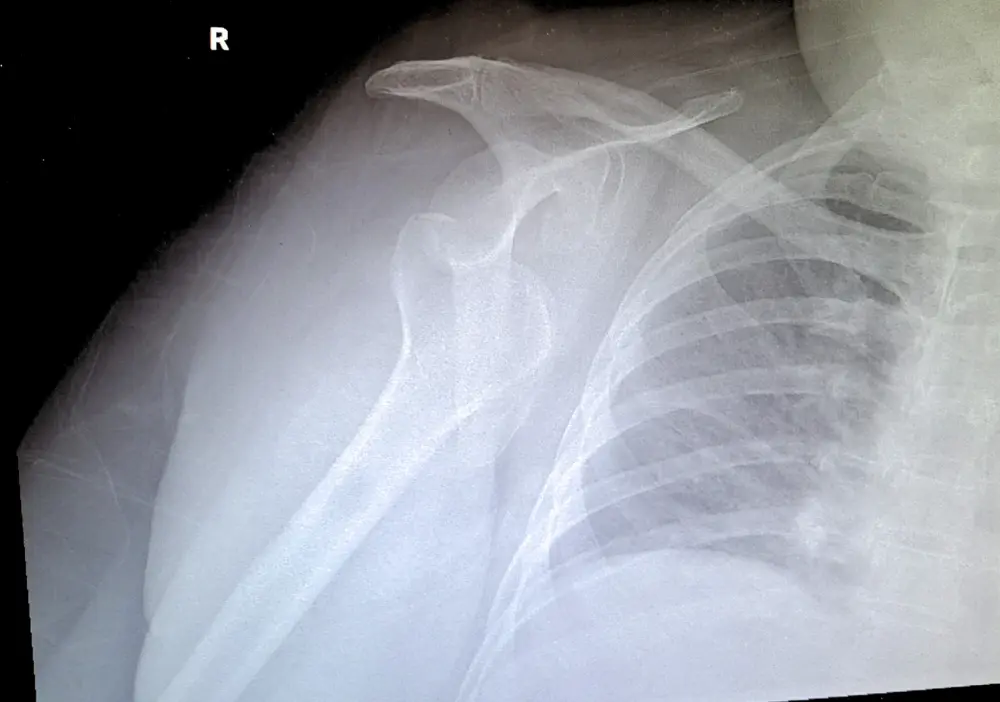

To diagnose a dislocated joint, your North Point Orthopaedics provider carefully examines the joint. You’ll have imaging tests like X-rays or an MRI so your provider can examine the damage to the joint and the tissues around it.